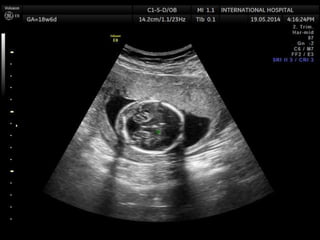

Edwards syndrome (Trisomy 18)

1st trimester

Increased nuchal translucency

2nd trimester

Multiple major anomalies

Single major anomaly + Trisomy 18 marker

Choroid plexus cyst + other anomalies

Early IUGR

IUGR

Cardiac defects

Muskuloskeletal findingd

-Clenched hands + overlapping index finger

Arthrogryposis

Rocker bottom foot

Clubfoot

Radial ray malformation

Cystic hygroma

Brain anomalies

Strawvberry shaped calvarium

Meningomyelocele

Facial anomalies

GI anomalies

SUA